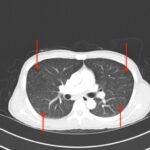

This is a case report of an HIV-positive patient with miliary tuberculosis (MTB). He presents to the emergency department (ED) two-weeks following the initiation of antiretroviral therapy (ART) with worsening cough, fevers, and malaise. The patient was diagnosed with Tuberculosis-Immune Reconstitution Inflammatory Syndrome (TB-IRIS) and subsequently treated with corticosteroids, resulting in clinical improvement over a two-week in-patient hospitalization. This case report details a rare case of TB-IRIS, a clinical diagnosis without universally agreed upon criteria. It also demonstrates a classic miliary pattern of disseminated tuberculosis on chest radiography.